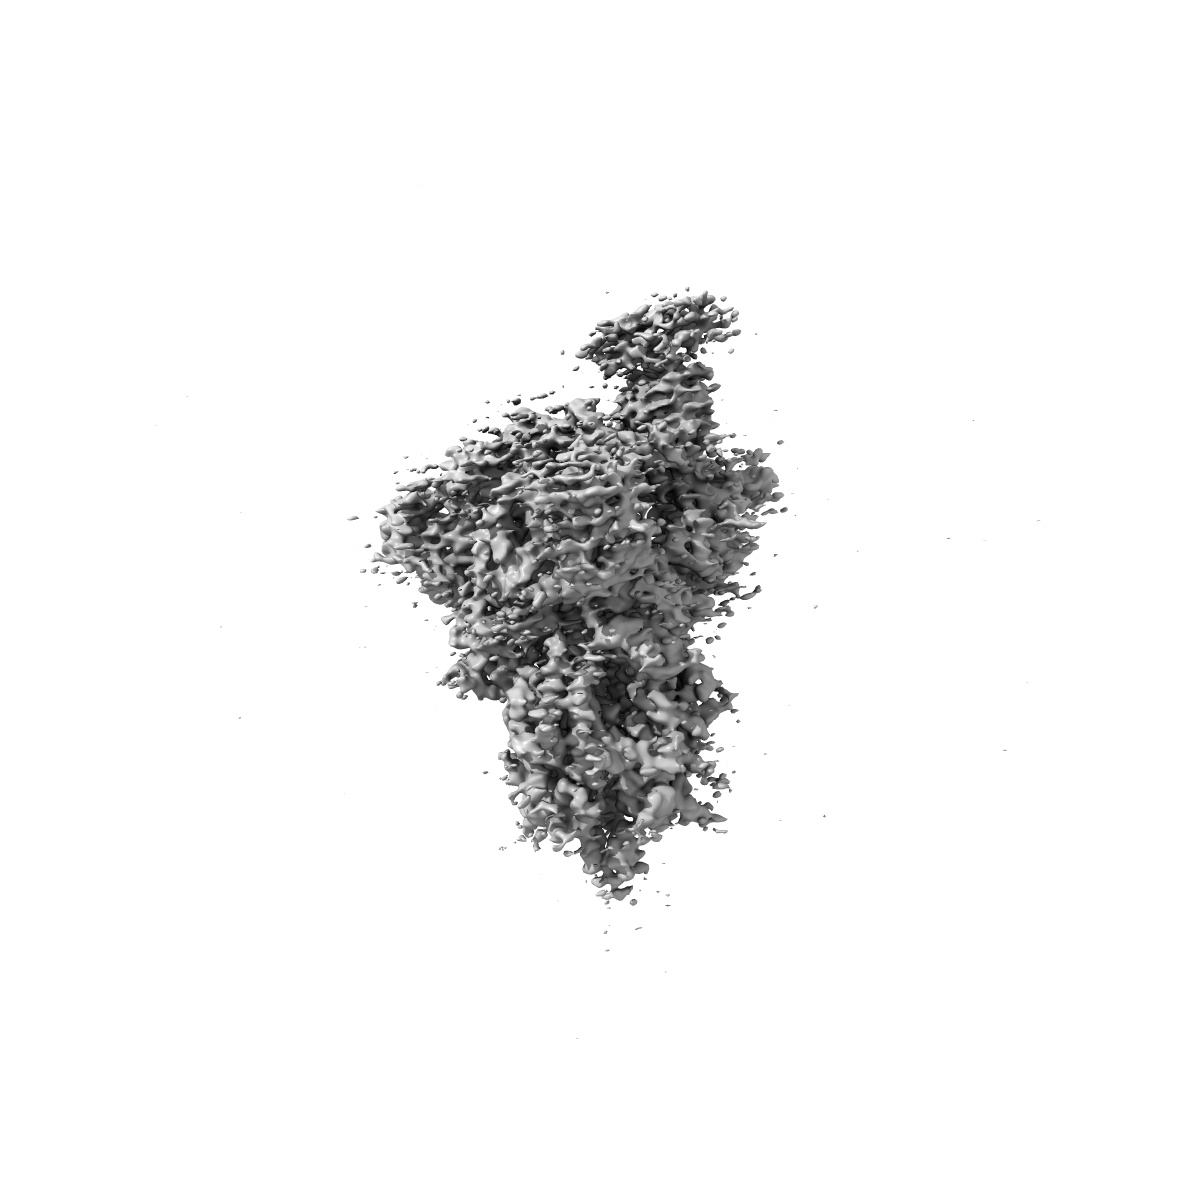

EMD-22913

Structure of the SARS-CoV-2 S 6P trimer in complex with the ACE2 protein decoy, CTC-445.2 (State 1)

Single-particle3.9 Å

Sample: Ternary complex of CTC445.2 inhibitor with SARS-CoV-2 S 6P glycoprotin